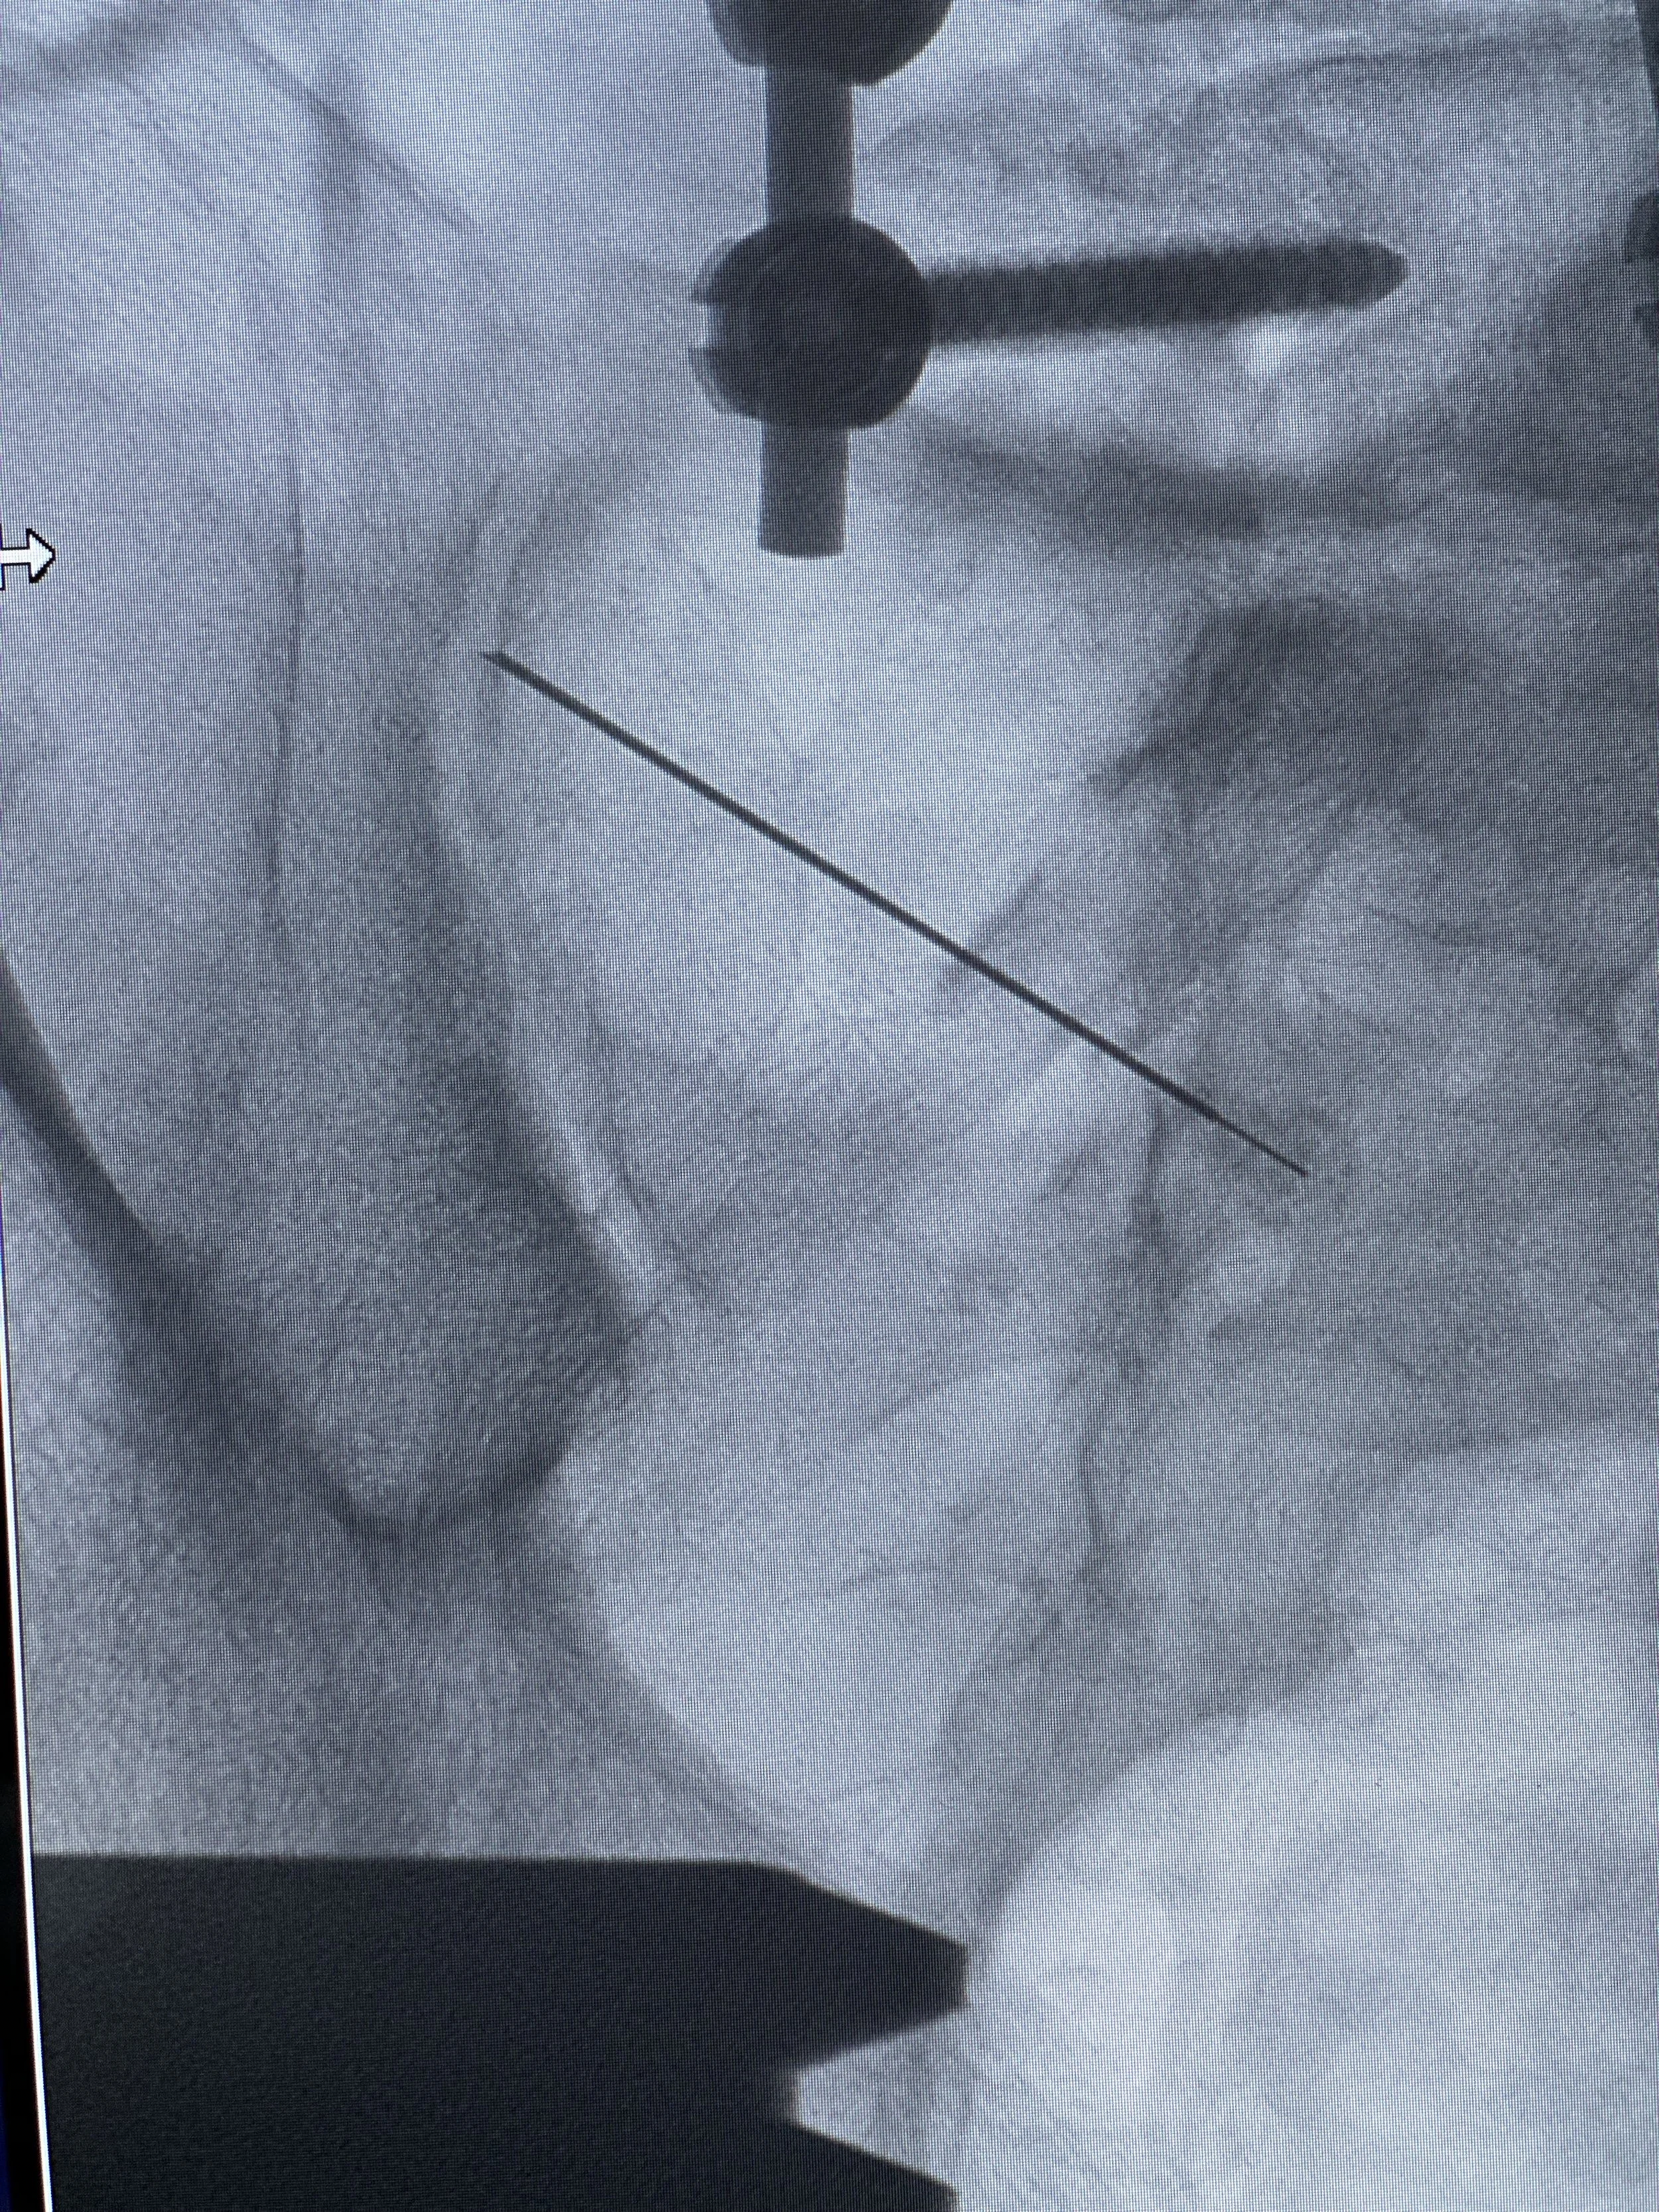

Cirugía de mínima invasión

COLUMNA VERTEBRAL

Cirugía de alta complejidad

MÉDULA ESPINAL